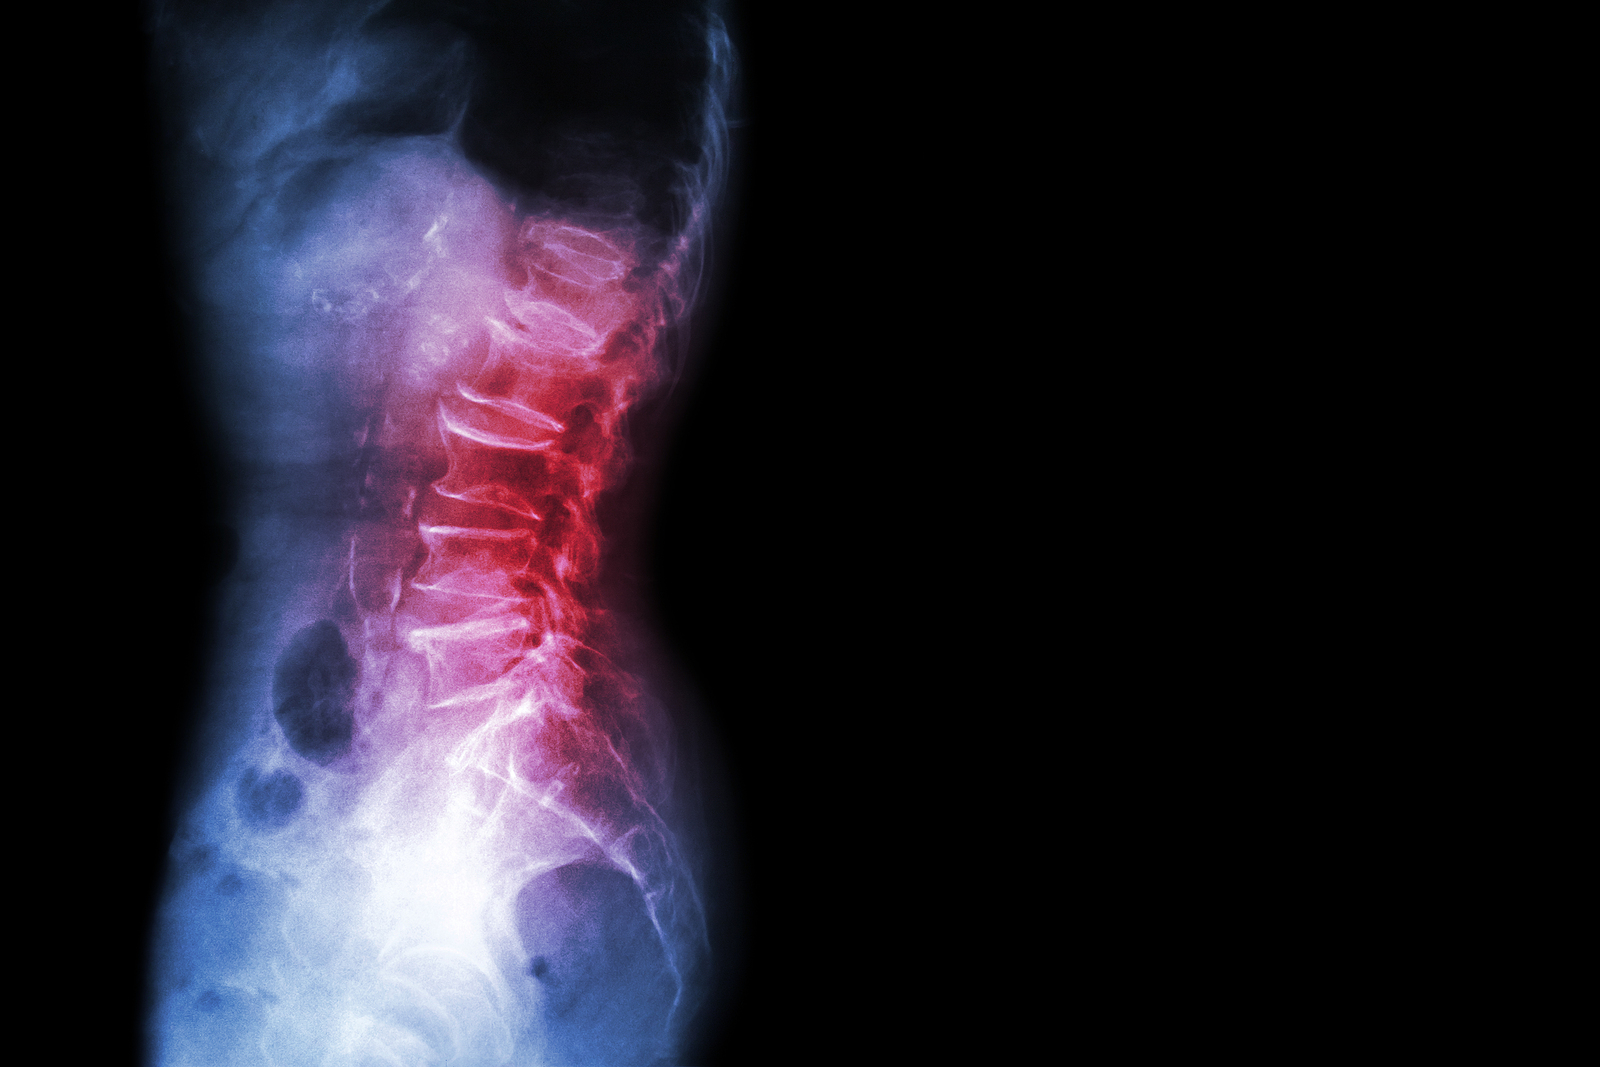

Anatomy

What Makes Up the Lumbar Spine?

The human spine is made up of 24 spinal bones, called vertebrae, as well as the sacrum and the coccyx. The sacrum is a triangular bone near the bottom of the spine and the coccyx is more commonly known as the tailbone.

Vertebrae are stacked on top of one another to create the spinal column. The spinal column gives the body its form and helps sustain an upright position.

The lumbar spine—where pain is often experienced—is made up of five vertebrae positioned near the bottom of the spinal column. Doctors often refer to these vertebrae as levels L1, L2, L3, L4 and L5. The ‘L’ refers to ‘lumbar’. The lowest vertebra, L5, is connected to the top of the sacrum—a triangular bone at the base of the spine that is located between the two pelvic bones. Some people are born with an extra or sixth lumbar vertebra called L6. Having an extra vertebra doesn't usually cause physical problems.